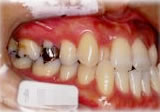

初診時年齢31歳7ヶ月。下顎側方偏位による咬合不全を主訴に来院。

顎変形と診断し、外科的処置を併用して治療。

左側面 左側面 左側面